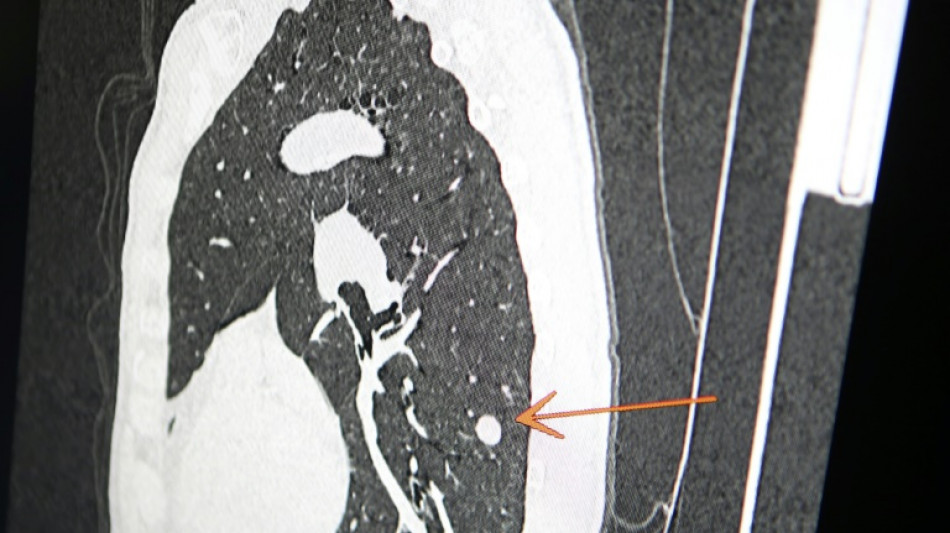

"Usted tiene cáncer", mensaje erróneo y aterrador a cientos de pacientes de una clínica en Inglaterra / Foto: © AFP/Archivos

Una clínica del norte de Inglaterra dio un gran susto a cientos de pacientes al enviar el mensaje "diagnóstico: cáncer de pulmón agresivo con metástasis" en lugar de sus buenos deseos de Navidad, informó el diario The Sun el jueves.

Según The Sun, entre los destinatarios del mensaje figuraba Chris Reed, un padre de familia de 57 años, que esperaba resultados de análisis para determinar si padecía cáncer de pulmón.